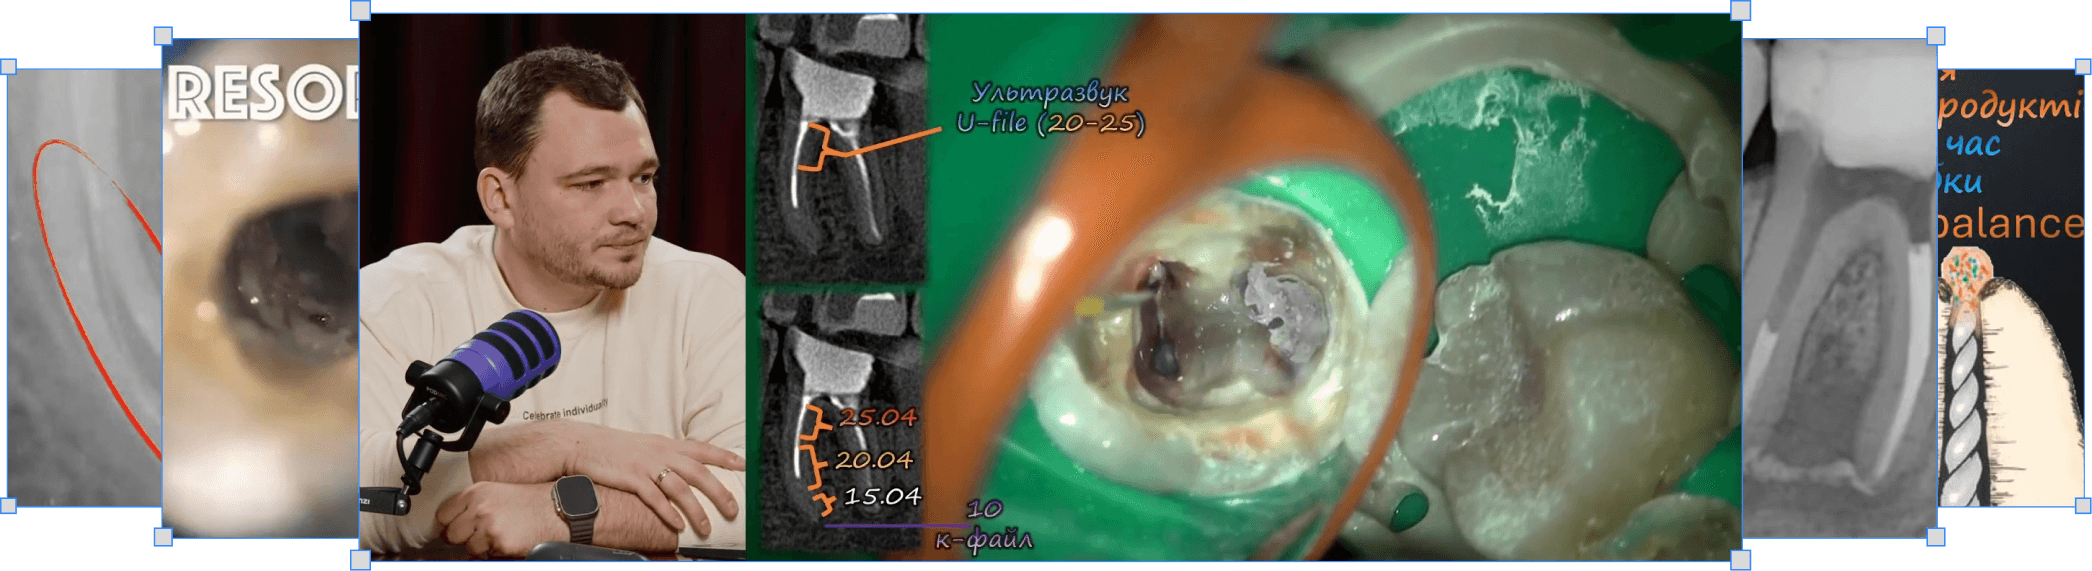

Розпломбування резорцин-формалінових зубів

Микола Сорухан

Розпломбування резорцину

Чіткі протоколи видалення резорцин-формаліну

Сходинки. Тактична карта обходу (MB-, ML-, DB-, DL-канали)

Продавлювання текучого сілера під гарячою гутаперчею